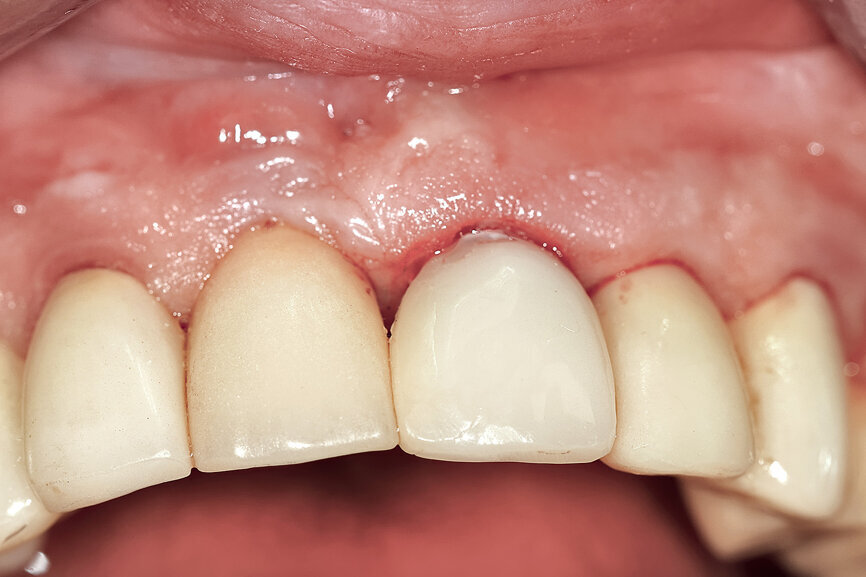

Fig. 29: The definitive restoration exhibited excellent retention of the soft-tissue profile.

Fig. 30a: The occlusal view revealed the volume maintained with

the soft-tissue cervical contours (a), and the lateral retracted view revealed an excellent soft-tissue emergence profile (b).

Fig. 30b: The occlusal view revealed the volume maintained with

The initial plan was for immediate extraction, immediate placement and immediate restoration. Therefore, it was essential to measure the implant’s stability with an objective technology, RFA, which provides an ISQ value utilising an implant-specific SmartPeg (Osstell; MEGA ISQ, MegaGen). The baseline ISQ value (76) confirmed sufficient initial stability to place an immediate restoration (Fig. 25). The prefabricated CAD/CAM abutment was then secured to the implant, and a postoperative periapical radiograph confirmed successful sub-crestal placement for this platform-switched design (Fig. 26a). The transitional acrylic restoration was then placed and examined for any occlusal interferences (Fig. 26b). It was important that the restoration be out of occlusion to avoid premature forces that could complicate integration. The soft-tissue contours were excellent, and no sutures were required, since no flap was raised (Figs. 26c & d). After a period of eight weeks, the implant stability was measured to be at 80 ISQ, confirming that the integration process had continued to progress successfully and that the implant was ready for the definitive restoration. An intra-oral scanner and scanning abutment were then utilised to capture the position of the implant and soft-tissue emergence profile. The post- operative CBCT scan revealed the intact crescent shape of the root membrane (Figs. 27 & 28). The definitive restoration was then delivered and exhibited excellent retention of the soft-tissue profile (Figs. 29 & 30).